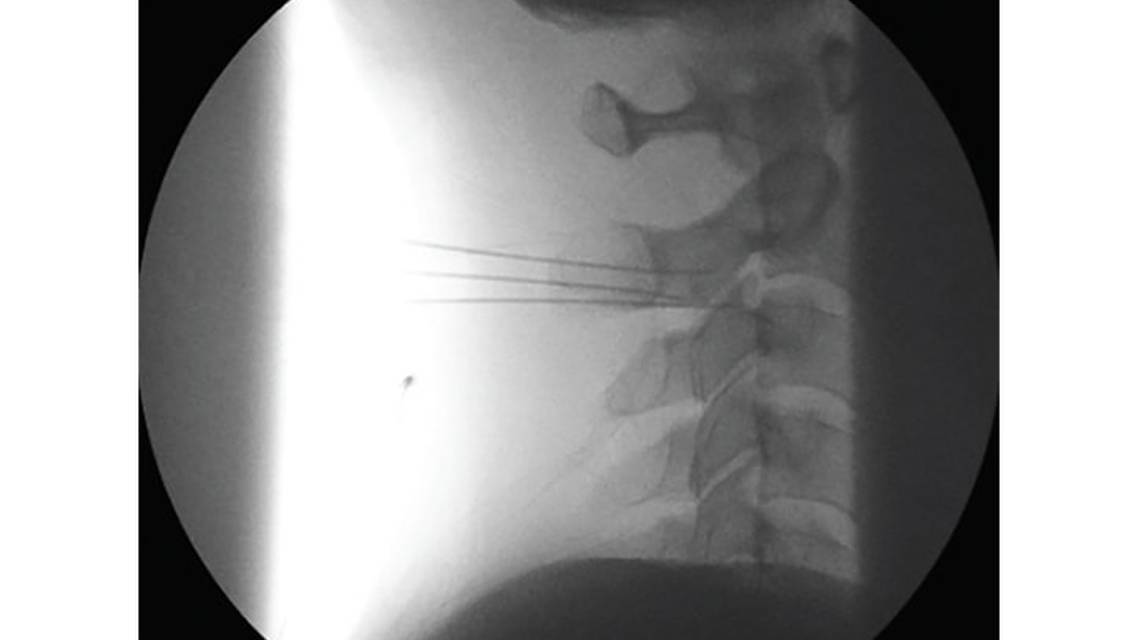

In both occipital neuralgia and cervicogenic headache, ICHD-3 diagnostic criteria include resolution of headache after appropriate diagnostic anesthetic block. Occipital neuralgia blockade can be performed in the clinic with a greater and lesser occipital nerve block.9 Ultrasound-guided blockade can also be performed to target proximal sites of the greater and lesser occipital nerve at C1 and C2.10 Cervicogenic headache is thought to be largely mediated by sensory nerve branches innervating C1-2, C2-3, and C3-4 cervical facets. Referral to a pain interventionalist can be considered for a fluoroscopy-guided block of the atlanto-axial joint, third occipital nerve (Figure 1), and upper cervical medial branch nerves.11-13